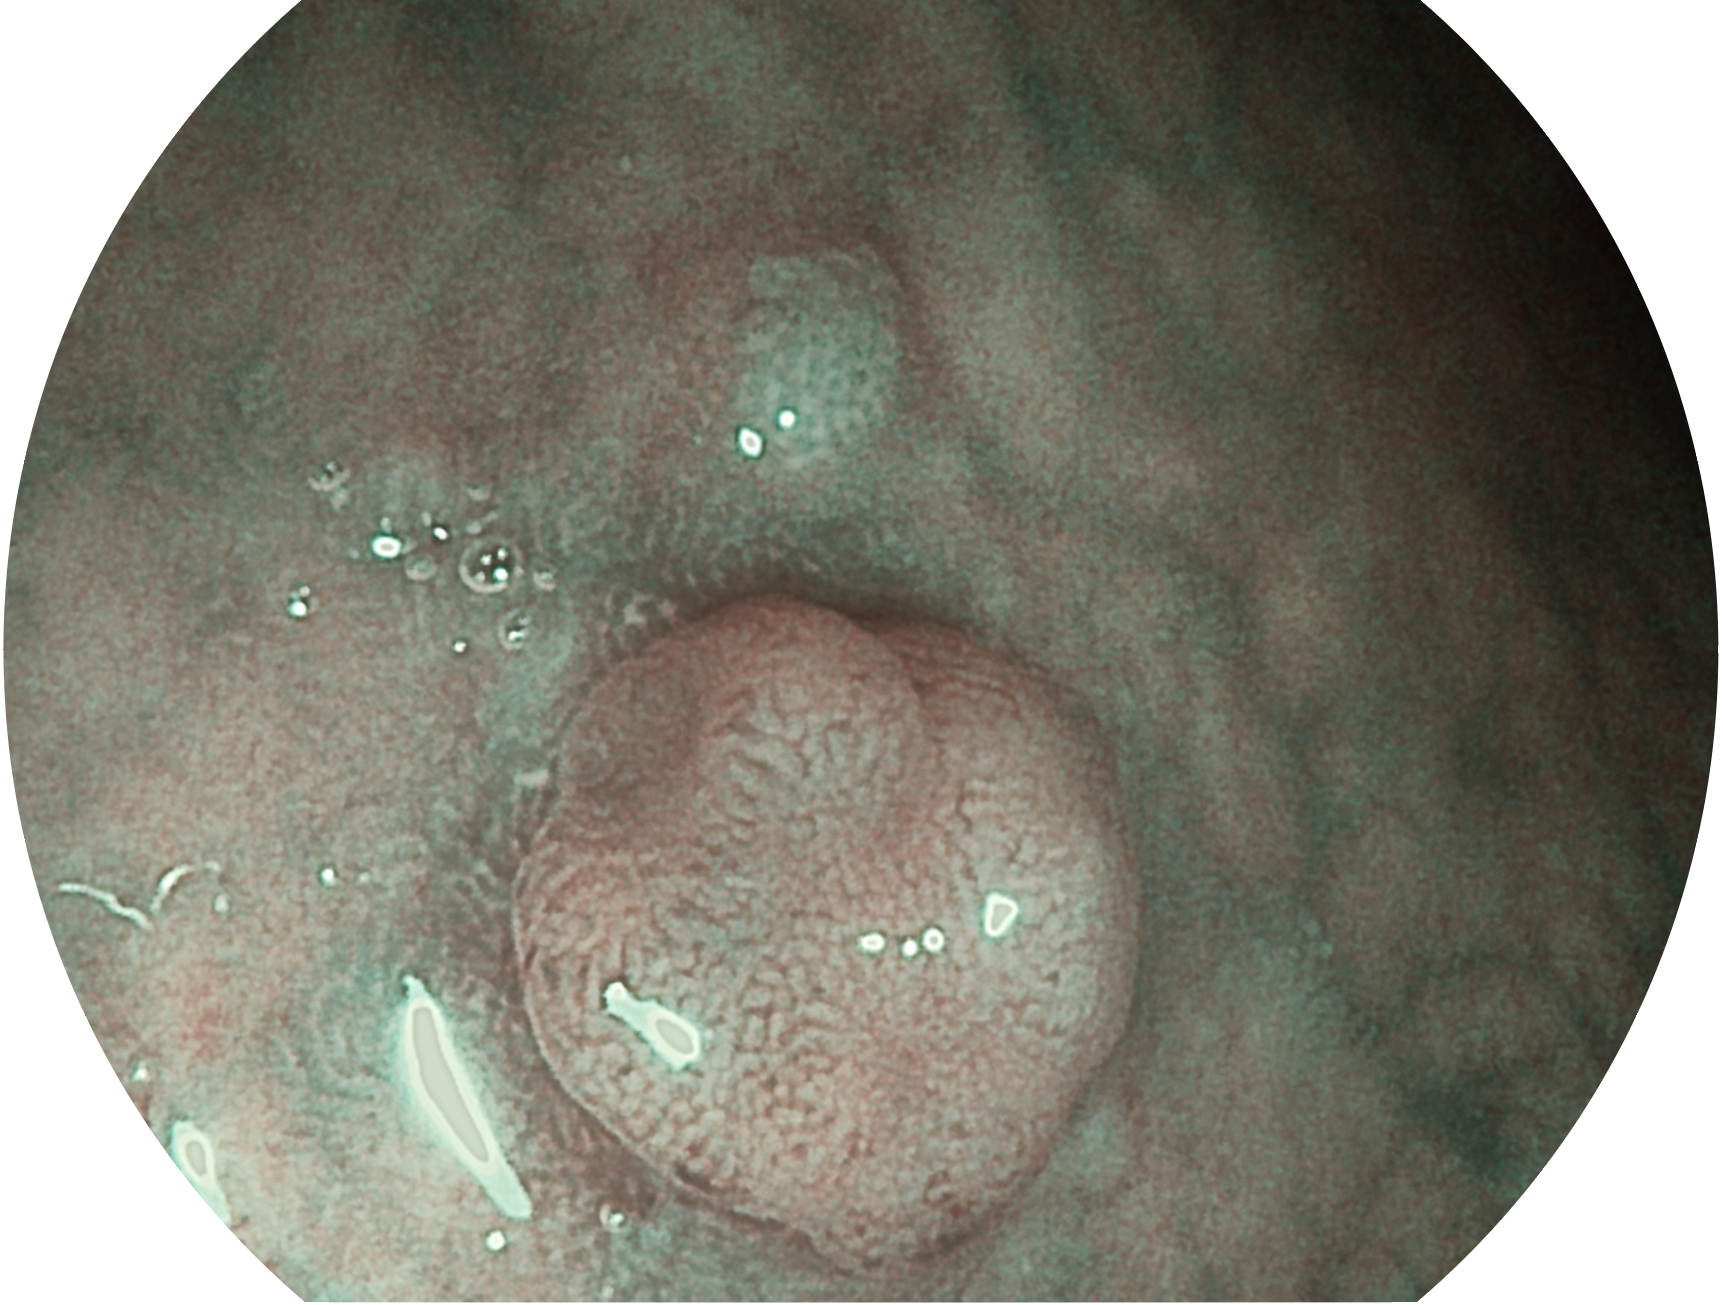

開立新開發(fā)的內(nèi)鏡染色技術(shù),主要是基于多波長(zhǎng)LED 光源的開發(fā),VLS-55Q 四波長(zhǎng)LED 光源是由四個(gè)不同顏色的LED光按照相應(yīng)照明模式所規(guī)定的特定發(fā)光比例進(jìn)行合束后形成,合束后形成的照明光的光譜由紅光、綠光、藍(lán)光及藍(lán)紫光這四個(gè)不同的波段范圍構(gòu)成。具有更高光譜自由度,通過(guò)光譜比例的控制,實(shí)現(xiàn)了聚譜成像技術(shù),英文全稱為“Spectral Focused Imaging, SFI”,縮寫為“SFI”和光電復(fù)合染色成像技術(shù),英文全稱為“Versatile Intelligent Staining Technology, VIST”,縮寫為“VIST”。